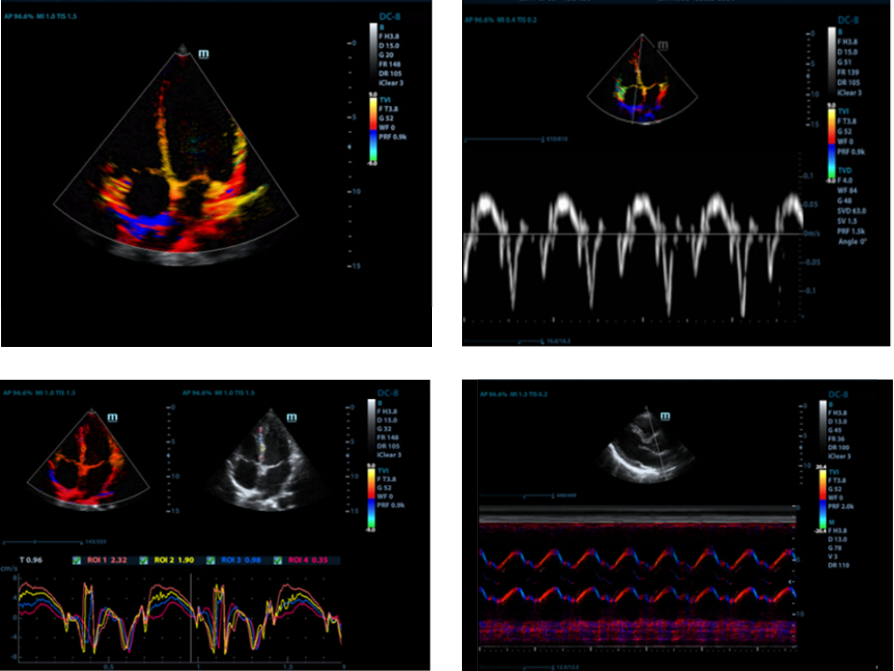

TDI

El diagnóstico por imagen en modo doppler tisular (TDI) permite evaluar cuantitativamente el movimiento miocárdico local y su función, proporcionando así modos TDI para un diagnóstico más rápido y directo.

Auto LV

Procedimiento de medición simple del ventrículo izquierdo mejorado gracias a la función de seguimiento automático y fácil corrección manual.